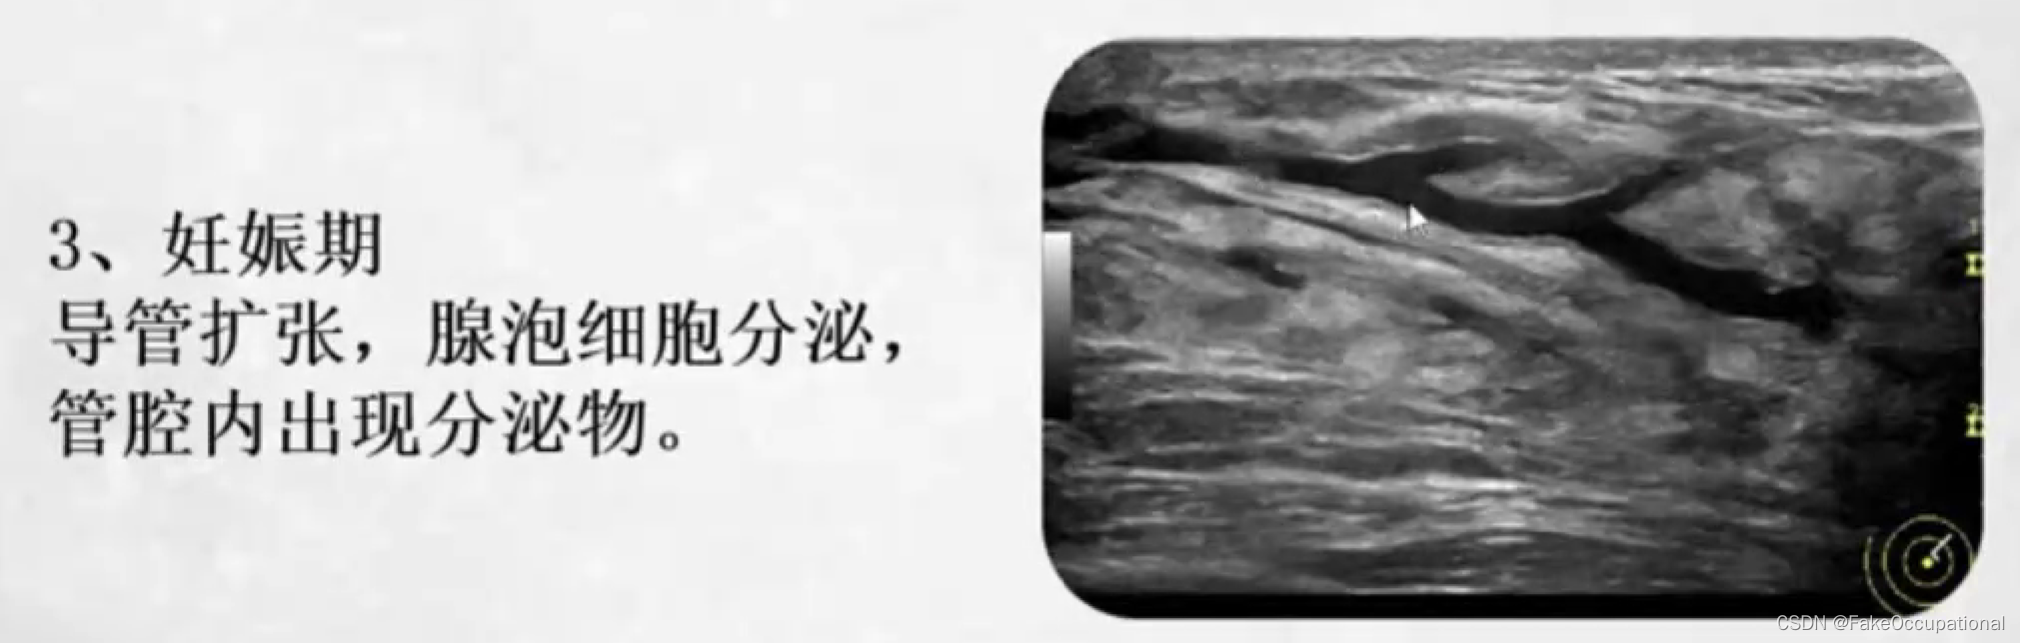

乳腺的生理解剖概要

乳腺的生理解剖概要